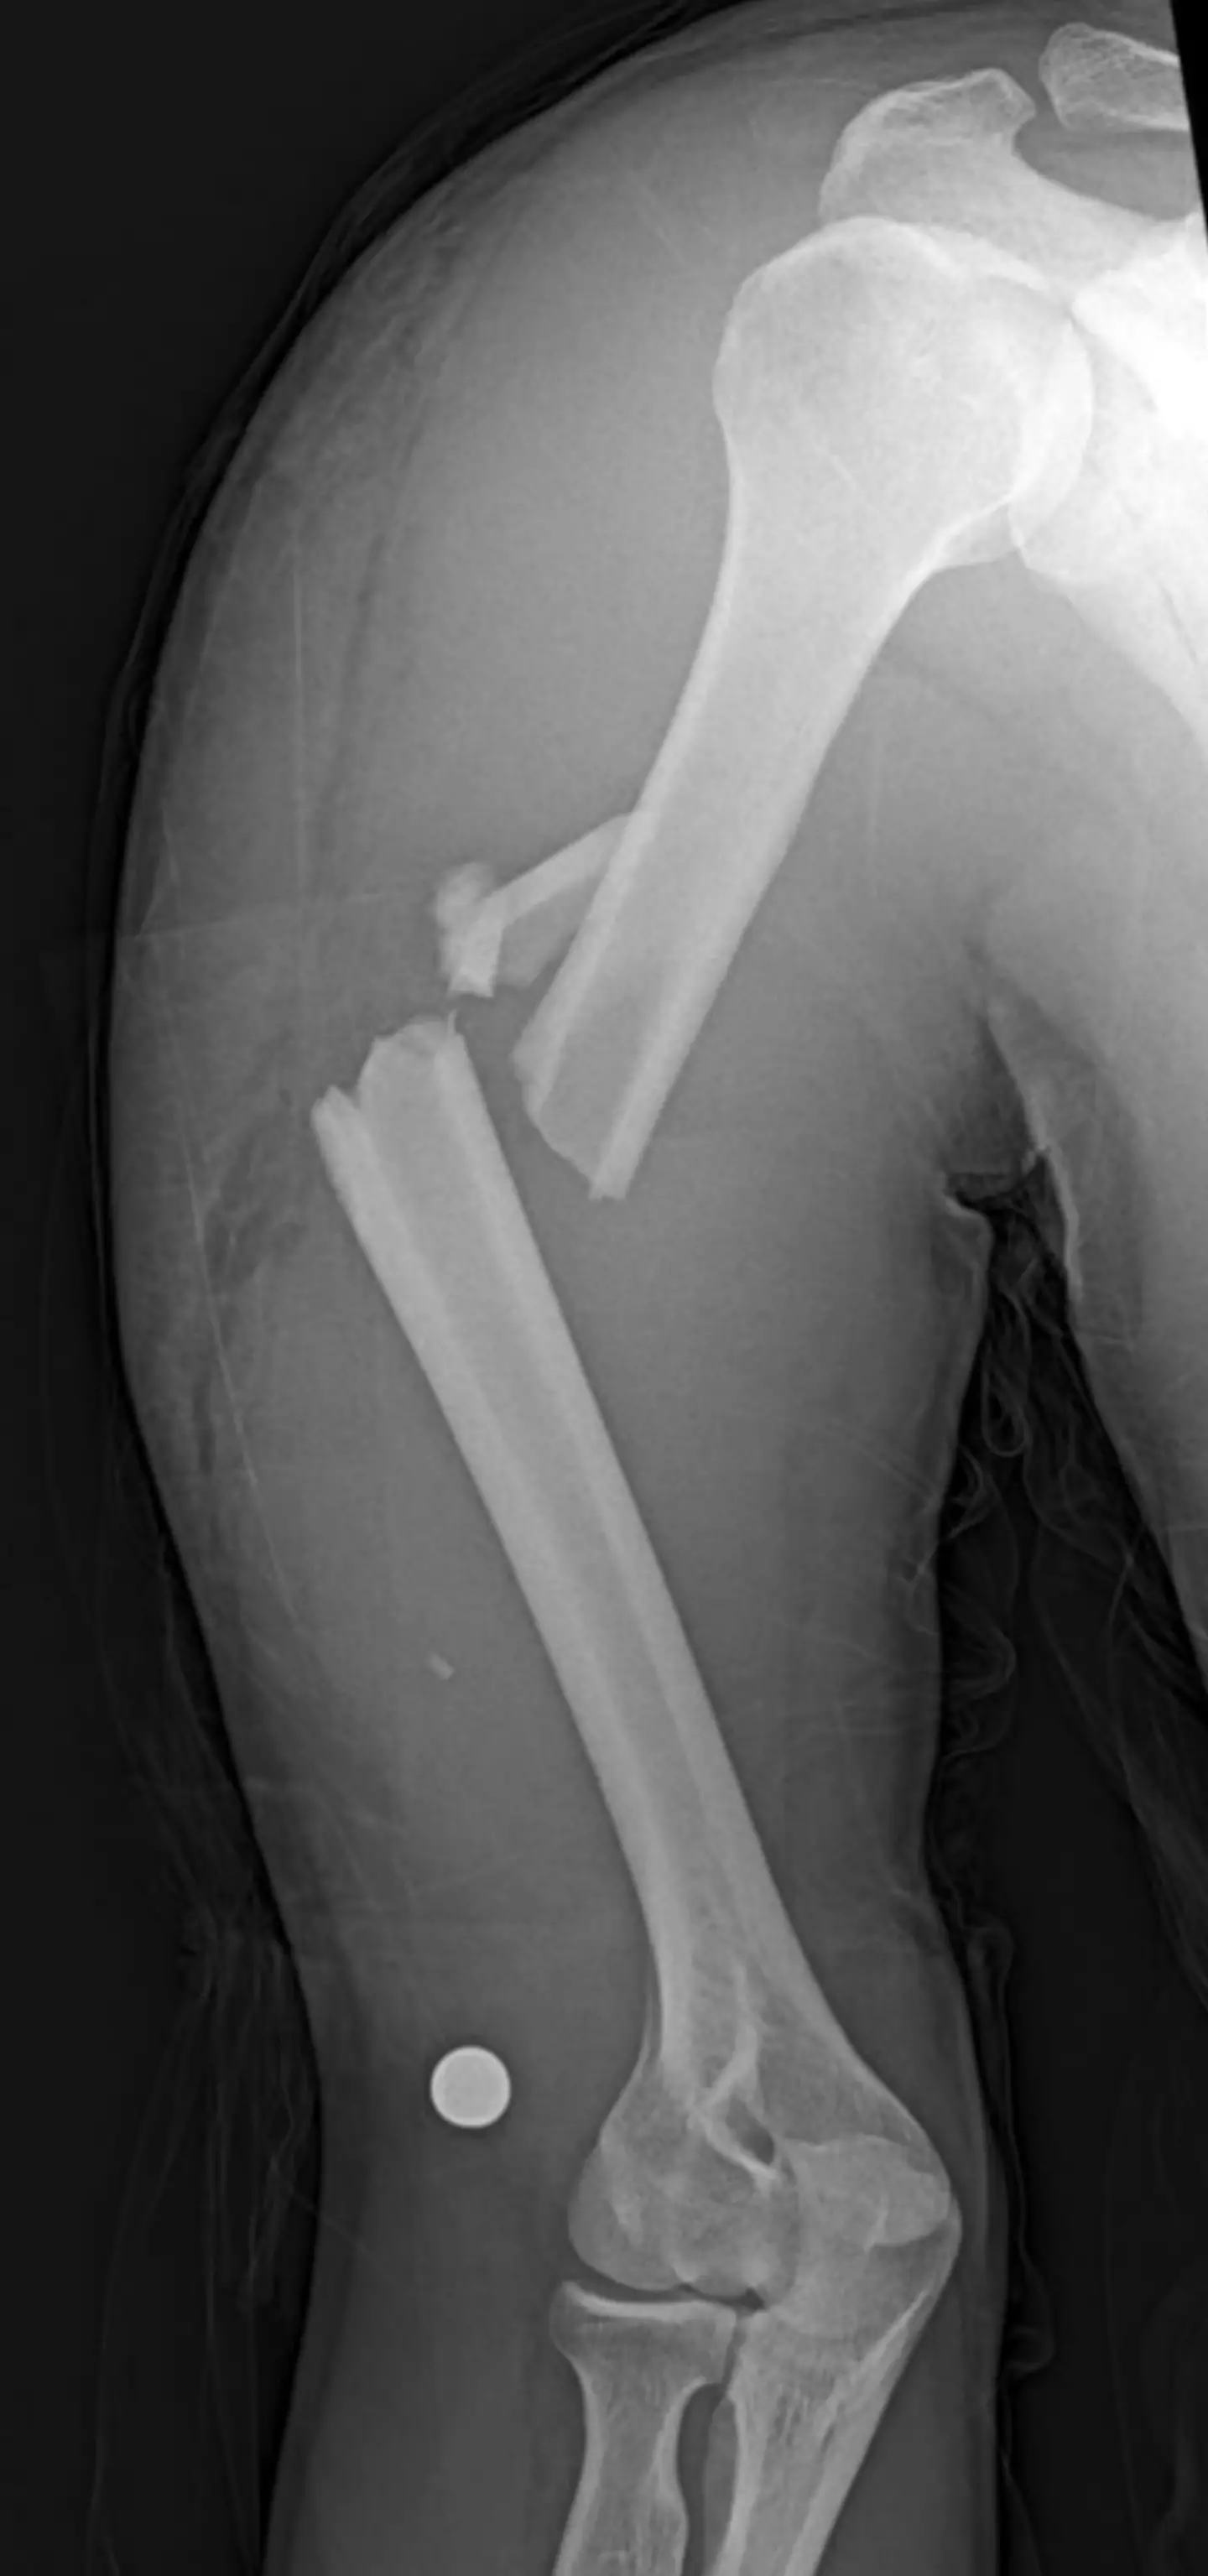

Why some people more likely to break a bone, explained

"We all know people who seem to trip and fall frequently but then bounce back up, and laugh it off," Dr Hussain recently told LADbible, adding: "Conversely, someone else trips over a curb and ends up in a cast."

"So why does this happen? Turns out, it’s not all random or down to divine protection," he continued.

Explaining how the strength of your skeleton is something which comes down through DNA, Dr Hussain explained: "Bone strength is largely inherited. That includes how dense your bones are, how well your body processes calcium, and even how your skeleton is built.

"Some of us are naturally more prone to thinner bones — and those can snap more easily under pressure."